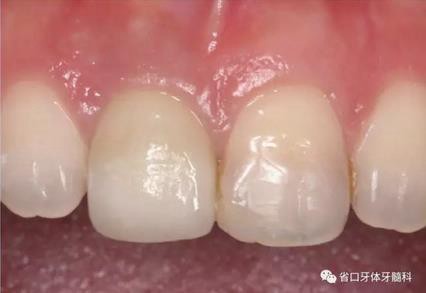

(4)最終修復(fù)與隨訪:經(jīng)過3個(gè)月左右的塑形,上頜右側(cè)中切牙臨時(shí)修復(fù)固位良好,菌斑控制良好,近遠(yuǎn)中齦乳頭充盈良好,齦緣水平及形態(tài)與 鄰牙相對稱。牙齦塑形穩(wěn)定后,以臨時(shí)修復(fù)體制作個(gè)性化轉(zhuǎn)移桿并取模轉(zhuǎn)移,并以原廠氧化鋯基臺(tái)制備個(gè)性化基臺(tái)及全瓷冠。正確就位最終基臺(tái),加 力30N·cm。制備粘接代型,去除多余粘接劑,以Unicem粘接固位上頜右側(cè)中切牙全瓷修復(fù)體。固化穩(wěn)定后,再次確定咬合無干擾。最終修復(fù)完成后 隨訪3個(gè)月及6個(gè)月,上頜右側(cè)中切牙種植修復(fù)固位穩(wěn)定,近遠(yuǎn)中齦乳頭充 盈良好,唇側(cè)齦緣水平穩(wěn)定。

圖34 負(fù)重3個(gè)月后

圖35 負(fù)重6個(gè)月后復(fù)診

上頜右側(cè)中切牙修復(fù)體固位良好,牙齦乳頭充盈良好,齦緣水平對稱 修復(fù)體與對側(cè)同名牙協(xié)調(diào)一致。外觀笑容美觀協(xié)調(diào)?;颊邼M意。X線檢查示 上頜右側(cè)中切牙種植體周穩(wěn)定骨質(zhì)包繞,唇側(cè)骨板>2mm,相鄰牙槽骨高度穩(wěn)定,基臺(tái)及修復(fù)體就位良好。分別根據(jù)Furhauser的PES和Bulser的WES 進(jìn)行美學(xué)評分,總分值為20,美學(xué)效果良好。